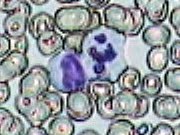

Imágenes tomadas de las preparaciones de los alumnos de 3º ESO sobre un frotis sanguíneo

180x135 píxeles